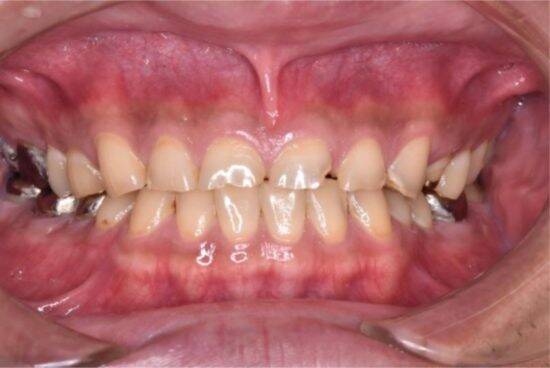

食事習慣や歯磨きなまけは、特に歯茎の状態に直結します。歯茎が炎症を起こして赤く腫れると、お口は一気に不健康な印象になります。お口が不健康だと、お顔全体の印象がくすんで見え、清潔感が失われます。

久しぶりにフロスを通して出血したり嫌な臭いがしても驚かないでください。それは歯茎が炎症しているサインです。毎日ケアをし続けることで、早ければ1~2週間で炎症が治まり、出血はなくなり、臭いも消え、引き締まった健康的なピンク色の歯茎に戻ります。もし、治りが悪い場合はすぐに歯科医院で相談をしましょう。